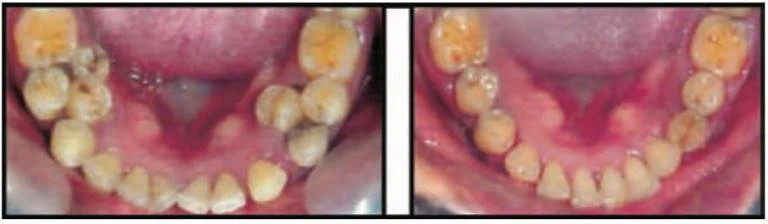

Răng mọc dưới mức khớp cắn: Chín phần trăm trẻ em trong độ tuổi từ 3 đến 12 tuổi có một hoặc nhiều hơn răng cối lớn mọc dưới mức khớp cắn. Nguyên nhân vẫn chưa rõ nhưng tình trạng này có tính gia đình và gặp phổ biến hơn ở một số nhóm dân tộc. Răng vĩnh viễn thay thế thường bị thiếu hoặc các răng này có thể bị cứng khớp. Chỉ định nhổ răng để chỉnh nha nếu việc làm đều những răng kế cận bị xáo trộn.

Răng mọc dưới mức khớp cắn thường bị cứng khớp trong xương và có thể phải dùng mũi khoan để cắt.